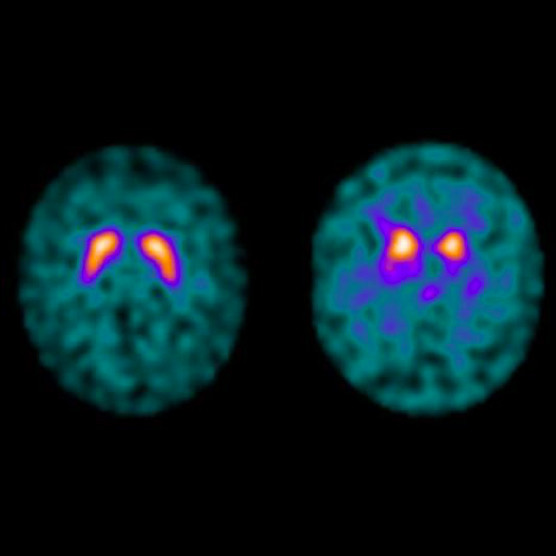

DaTSCAN Imaging Characteristics in iRBD Patients (n=12) Download

DaTSCAN Imaging Characteristics in iRBD Patients (n=12) Download What Is A Dat Scan Radiology It uses radioactive material to diagnose some diseases of the brain, especially those that. A datscan is a nuclear medicine imaging procedure. Questionswhat is datscan imaging?datscan takes detailed pictures of the brain, focusing on the cells. It requires an injection of a small. A brain datscan is a nuclear medicine scan. In 2011, the food and drug administration (fda) approved. What Is A Dat Scan Radiology.